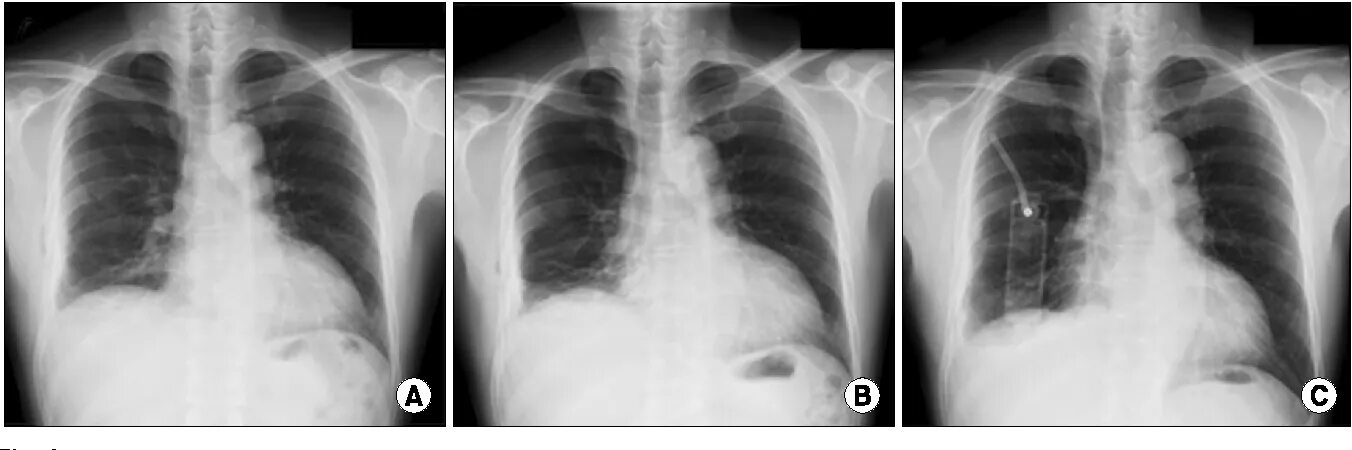

Коллабированное легкое при пневмотораксе